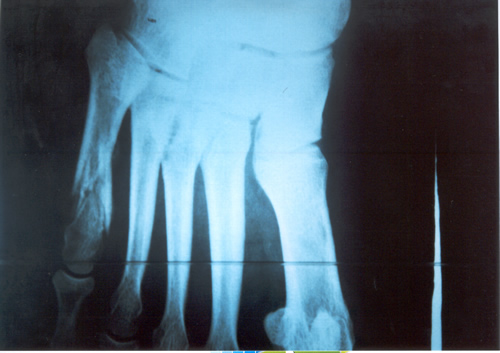

FRACTURA DEL QUINTO METATARSIANO

Generalmente la informamos como fractura de la cola del quinto metatarsiano, porque allí es el lugar de mayor frecuencia, especialmente en el deportista saltador. En nuestro estudio estadístico y para el libro de Traumatología en el Futbol ( edición 2005 Ed Akadia,)

observamos que la mayor cantidad de estas fracturas, fueron padecidas por los defensores centrales , atribuible esto al mecanismo de acción en el salto en ambas áreas, correspondiente a la función de dicho jugador. El caer, frecuentemente se genera una torsión en supinación en el momento de apoyar con la cara externa del pié, ora en terrenos desiguales ó bien con pérdida de la estabilidad en el aire, debido a la fricción con el contrincante.

Dicha caída desarticulada produce un esguince de antepié, con impacto sobre la cola del quinto y fractura secuelar. Puede escucharse ruido con dolor puntual, por lo que el jugador abandona el campo de juego.

En la generalidad de los casos, con una inmovilidad adecuada sin cargar el peso del cuerpo por 45 días suele consolidar la fractura. Depende del trazo de la fractura y en que lugar está ubicada en el hueso Dicho metarsiano presenta una irrigación sanguínea deficiente y es quizás la causa importante que impide consolidaciones seguras y en poco tiempo. Aún mas, si ocurre en un pié cavo varo, es decir en un pié con mucho arco interno distinto ú opuesto al apoyo anatómico del pié plano. Este es el jugador que padece esguinces a repetición de tobillo por exceso de arco del pié.

Si la fractura se ubica en el tercio medio de la diáfisis del hueso , ya no en la cola del quinto, el tratamiento incruento generalmente es exitoso. En nuestro caso y para esta patología nos estamos ocupando sólo de la cola del quinto.

Sin embargo, puede ocurrir que luego de la inmovilización sin apoyo del pié lesionado, y que el informe de las imágenes radiográficas y tomográficas, no demuestren un callo aceptable para el comienzo de la rehabilitación kinesiológica, está la posibilidad de la resolución quirúrgica.

También ésta, presenta dos alternativas. O bien disconforme con la imagen que arrojan los estudios se indica osteosíntesis de aquella mediante un tornillo ó bien si intentan con rehabilitación kinesiológica post inmovilización, recuperarlo a pesar de un callo endeble, puede ocurrir que no se logre lo deseado.

En este caso, si el jugador en varios intentos de probar en el campo de juego siente dolores o se genera dolor parecido al inicial luego de caídas repetidas, estaremos en presencia de un déficit de consolidación por retardo de la misma ó peor aún, seudoartrosis ó falsa articulación ó movimiento indeseable en el foco de la fractura que impide la total recomposición de la misma.

En este estadío es cuando no cabe duda que la indicación es la operación . Personalmente nosotros hemos realizado osteosíntesis con tornillo junto a injerto óseo en el lugar lesionado que es extraído de la cresta ilíaca de la pelvis. Elemento óseo éste con gran irrigación sanguínea que viene a alimentar el déficit del hueso metatarsiano. Siempre utilizamos inmovilización enyesada por 45 días. Habrá quien utilice ortesis y ello depende la casuística de cada cirujano. Pero esto ya es tema para otro artículo.